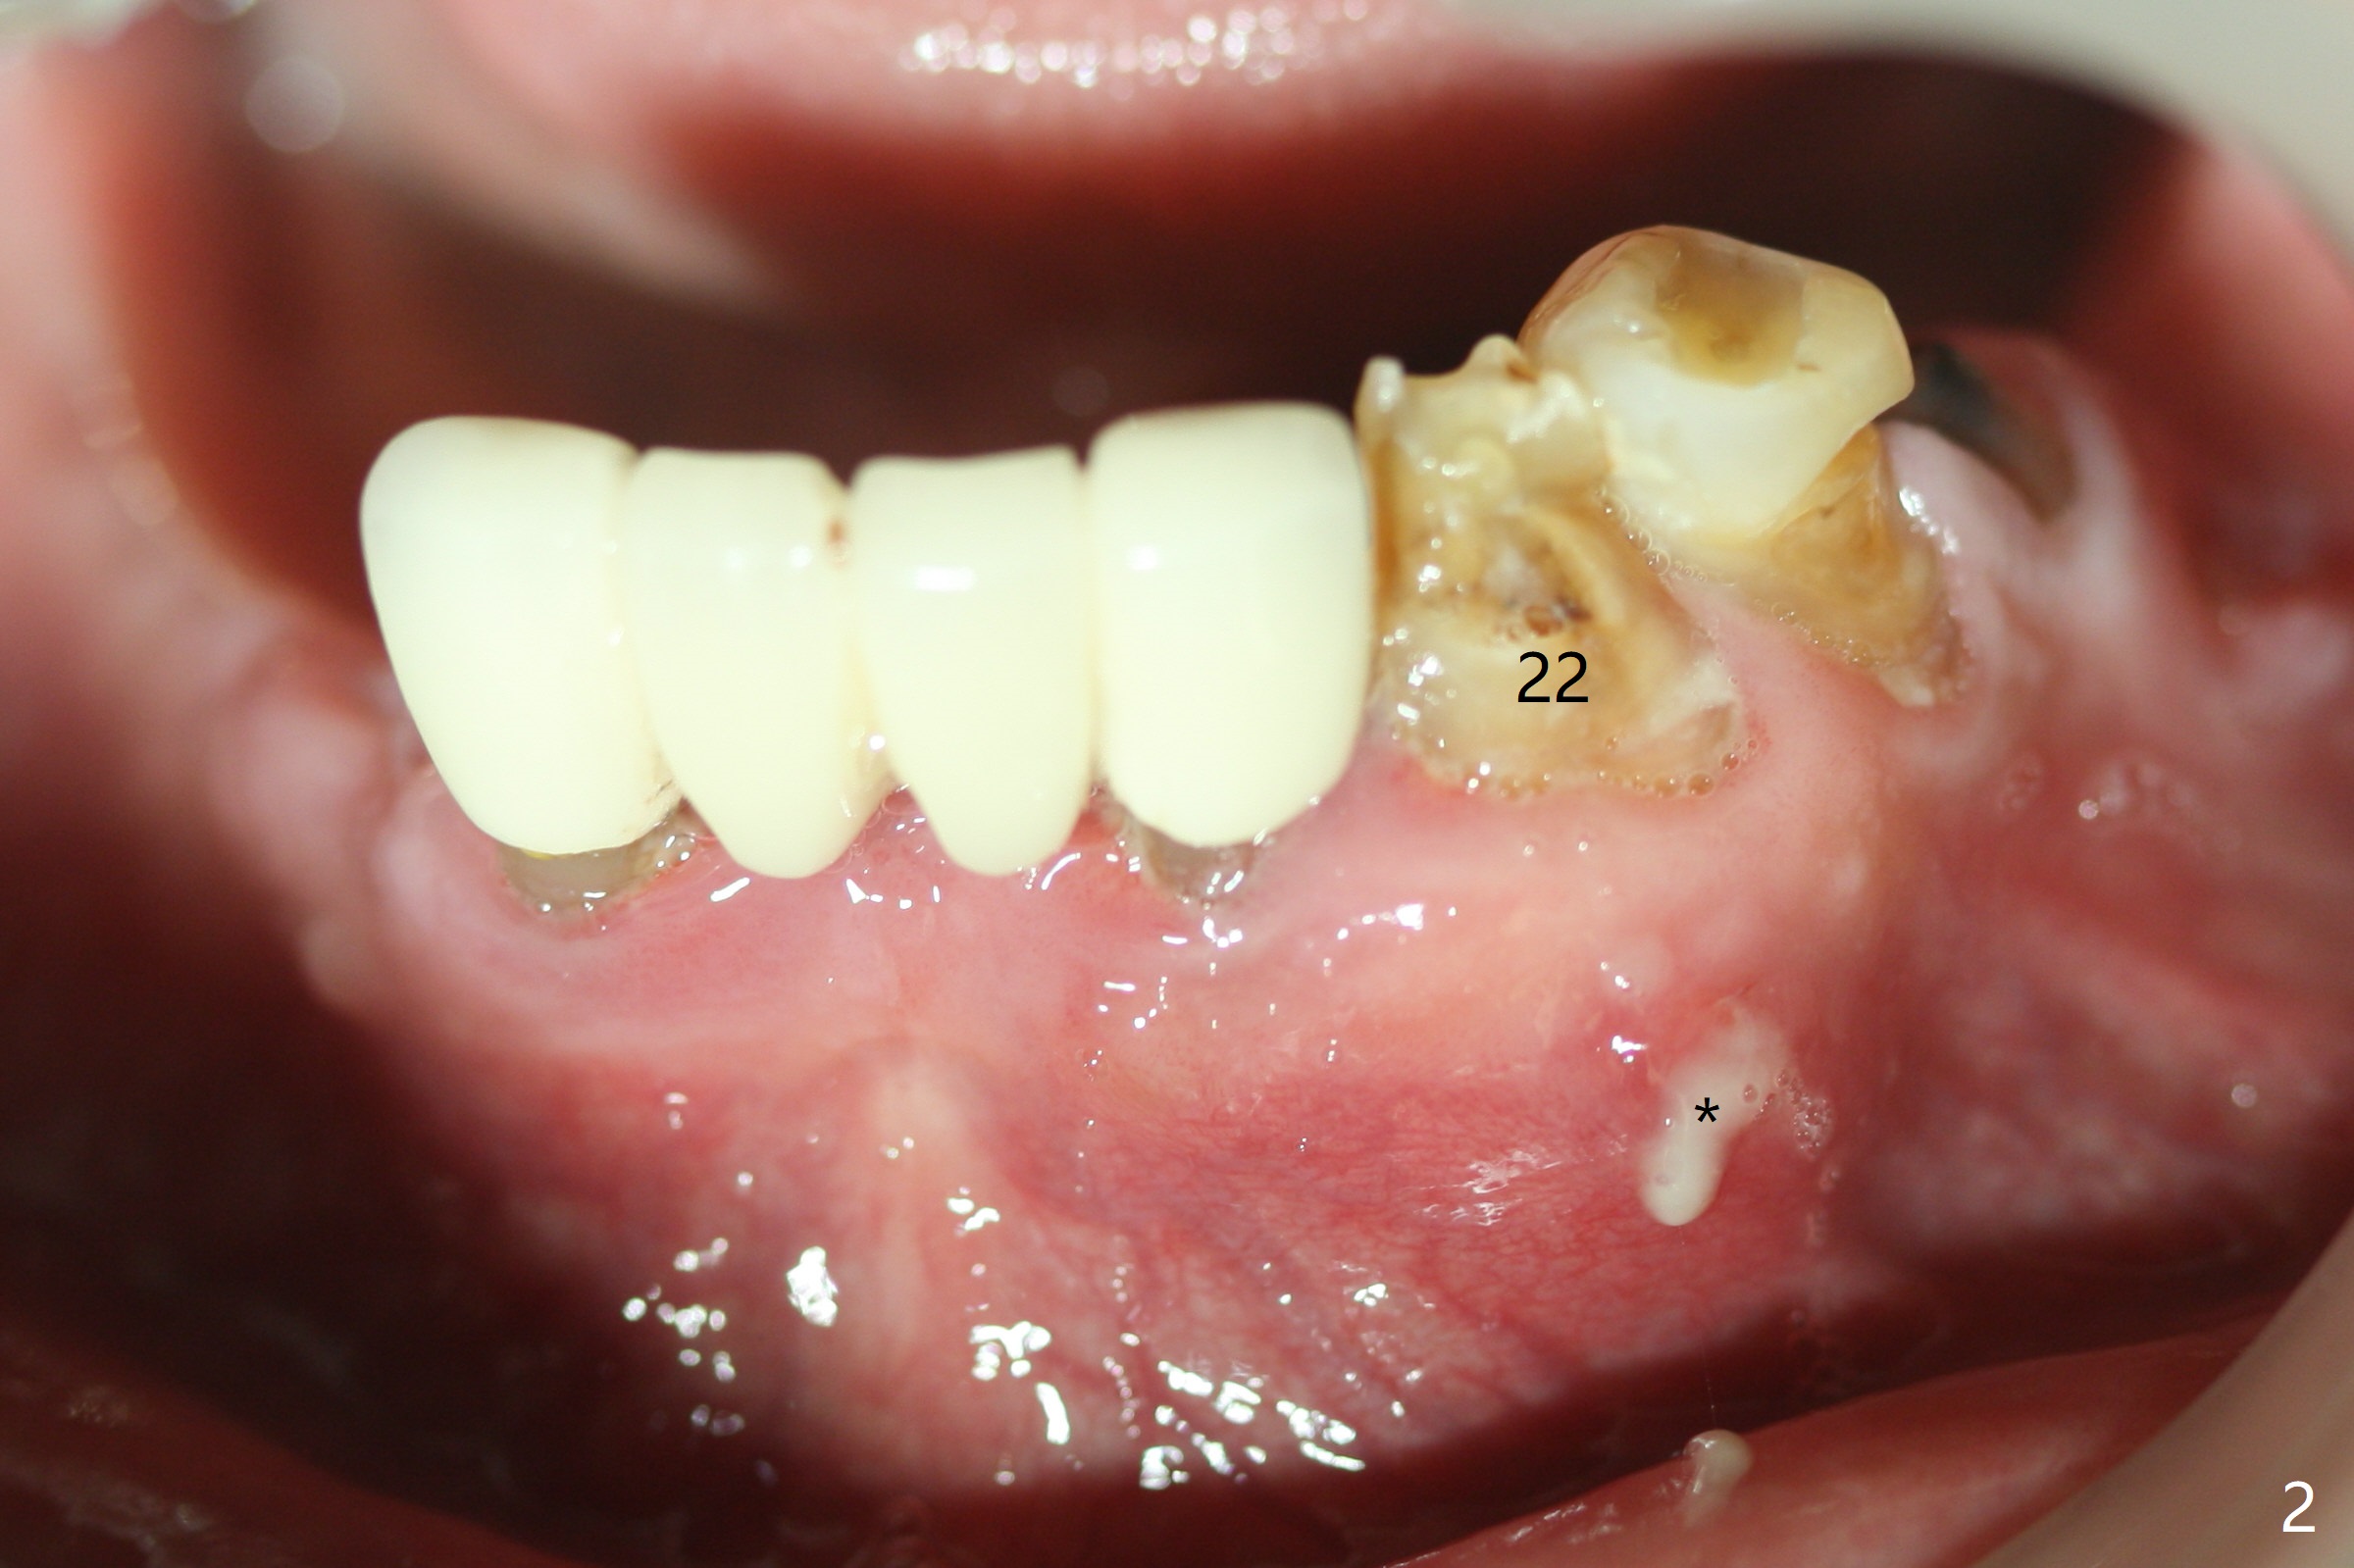

Abutments for Lower RPD

A 82-year-old man with poor dentition (upper and lower RPDs) returns to clinic for definitive treatment 2 weeks post socket preservation at #27 (with loss of the buccal plate, Fig.1). The bridge at #23-26 is mobile and to be removed. The tooth #22 appears to be restorable, but there is a buccal fistula (Fig.2 *). The root is out of the socket revealed by CBCT (Fig.5). Bone loss is severe at #20 (Fig.1,6). Three implants are going to be placed with guide at 27 or 26, 22 and 20 (Fig.3-6) with ball abutments for the lower RPD retention. Later the tooth #18 is found to be nonsalvageable.